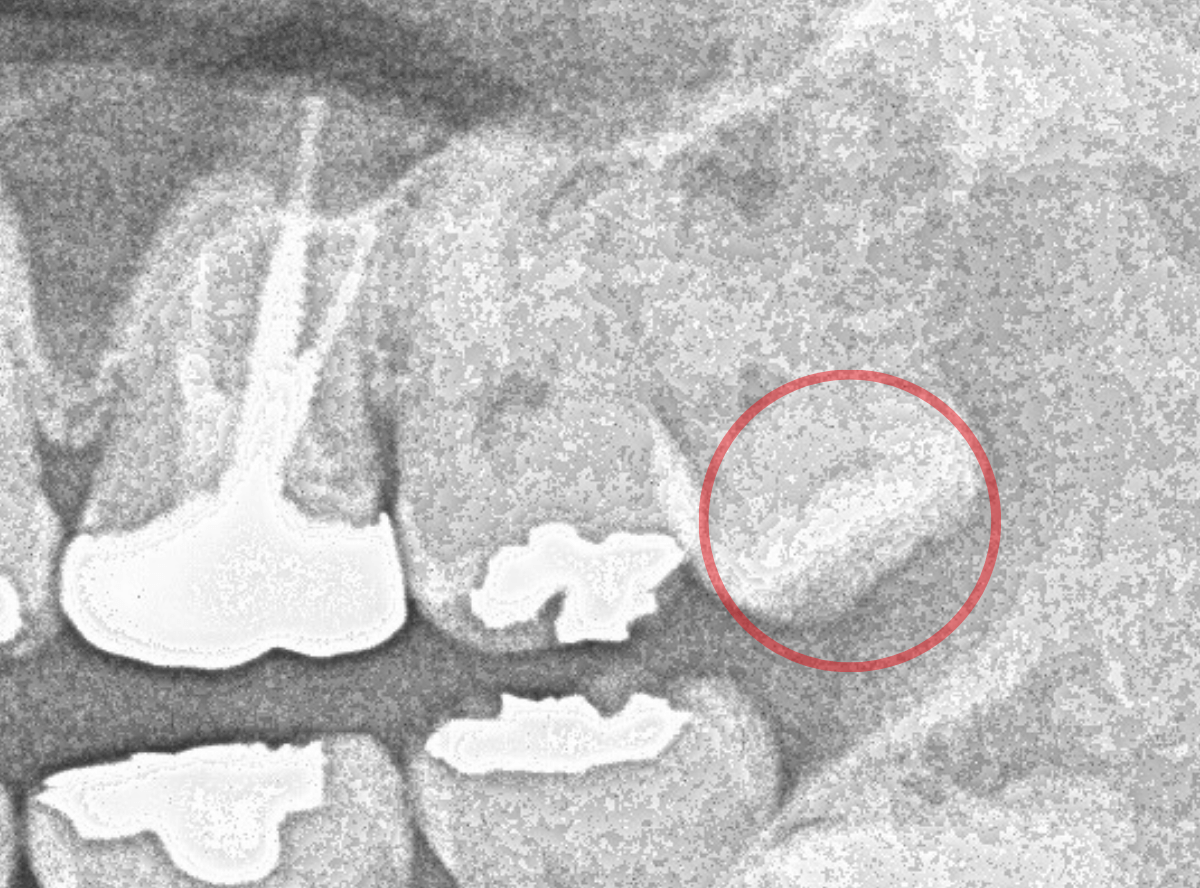

ここでは、比較的簡単なおやしらずの抜歯の例を中心にご紹介します。

このようなおやしらず、あなたはありませんか?